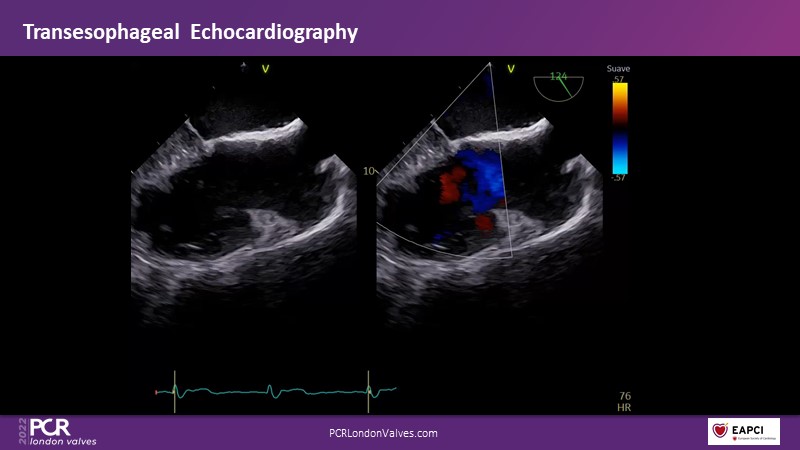

Watch this session if you want to learn tips and tricks that influence procedural strategy through a real-life case as well as anatomical factors that contribute to tricuspid valve complexity and choice of treatment, followed by the latest clinical data.

- To learn more about the anatomical factors that contribute to tricuspid valve complexity and choice of treatment

- To share tips and tricks that influence procedural strategy through a real-life case